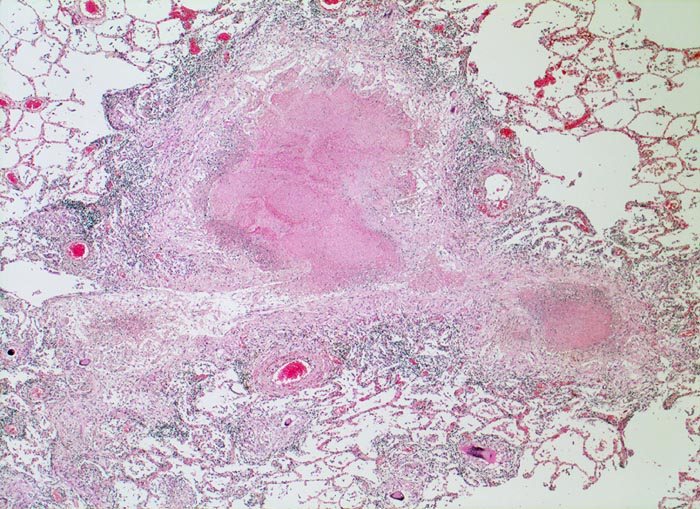

Das morphologische Bild ist äusserst variabel. Je nach Abwehrlage, Art und Geschwindigkeit der Ausbreitung entstehen unterschiedlich grosse, teils geschichtete Herde mit unterschiedlichem Grad an Epitheloidzellreaktion, zentraler Nekrose bzw. Vernarbung. Rein produktive Granulome ohne Nekrosen sind Zeichen guter Abwehrlage. Der Begriff Verkäsung bezieht sich auf den makroskopischen Aspekt von Nekrosen, der an Frischkäse erinnert. Exsudative nekrotisierende Granulome entstehen bevorzugt bei schlechter Abwehrlage. In späteren Stadien der Lungentuberkulose unterscheidet man produktive Phthisen mit azinös nodösen Gruppen von bronchogen entstandenen gering verkäsenden Streuherden (Präparat), zirrhotische Phthisen mit gering verkäsenden stark vernarbenden Herden und exsudative Phthisen bei schlechter Abwehrlage. Bei letzterer steht die Verkäsung im Vordergrund. Die bakterienreichen Herde entstehen teils hämatogen, teils bronchogen. Verkäsende Herde sind Ausgangspunkt für die Kavernenbildung. Kavernen stellen die wichtigste Quelle für die bronchogene Streuung dar.

• Tuberkulöse Herde ausgehend von vollständig oder partiell entzündlich zerstörten Bronchiolen in unmittelbarer Nachbarschaft von Arterien.

• Granulome mit zentraler käsiger Nekrose mit Kerntrümmern umgeben von einem Epitheloidzellwall und einem äusseren blauen Saum von Lymphozyten.